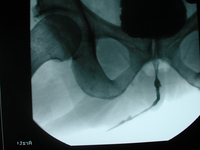

Röntgenbild einer langstreckigen Harnröhrenstriktur vor der Operation